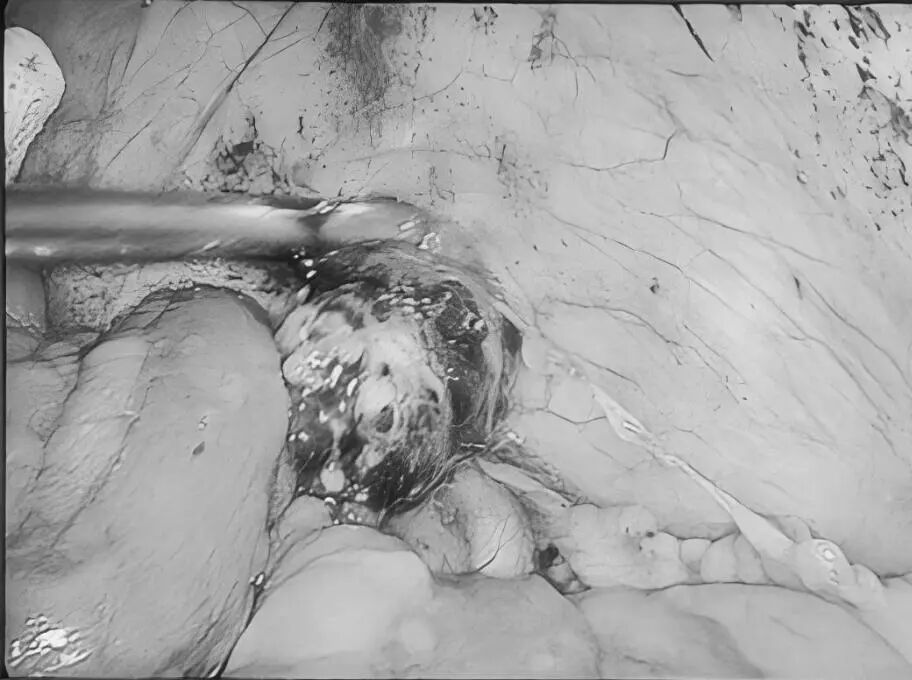

近日,贵州航天医院普外科开展了“呵护生命,你我相伴”第二届肿瘤患者联谊会。这场别开生面的联谊会,为肿瘤患者提供了一个相互支持、相互鼓励的平台,收获了大家的一致好评。 会上,普外科联合中医科、临床营养科组成专家团队,就肿瘤相关的科普知识、发病因素、治疗手段、护理方法、营养指导、造口护理、术后中药治疗和注意事项等内容进行了深入浅出的讲解。 副院长廖江荣致辞 普外科主任梁跃发言 健康讲座 在交流互动环节,患者及家属们踊跃发言,提出了在治疗与康复过程中遇到的各种问题与困惑,医护人员耐心为患者及家属答疑解惑,提供了切实可行的指导与帮助,让大家获益良多。 此次活动开展,让这些患者在与病魔抗争的过程中不再感到孤单与无助,进一步增强了他们在康复之路上的信心和力量。未来,贵州航天医院普外科将继续秉承“关爱患者、守护生命”的服务理念,与患者携手共进,在抗癌这条充满挑战的道路上坚定前行,为更多肿瘤患者照亮生命的希望之光。 贵州航天医院普外科专家团队 梁 跃 普外科主任 主任医师 临床擅长:对普外科各类肿瘤手术具有丰富的临床经验。 毕业于遵义医学院,遵义市医学会小儿外科学分会常务委员,遵义市肛肠协会理事,遵义市医学会核医学分会(第二届)委员会委员;荣获第三期“黔医人才计划”优秀学员称号;主持市级课题1项,完成省级课题1项,在国内各类刊物上发表论文10余篇。 钱科洪 普外科 副主任医师 临床擅长:从事普外科临床工作30余年,对各类普外科疾病的诊治、乳腺、甲状腺、胃十二指肠、结直肠等疾病及疑难杂症具有丰富的临床诊疗经验。 贵州航天医院普外科简介 基本情况 贵州航天医院普外科成立于1968年,前身属于航天部O61基地3417医院外一科,1998年3417医院、3427医院合并后更名为普外科,下设胃肠外科、肛肠外科2个亚专业科室,拥有在全市较为先进的专科设备和技术,是中国疝病专科联盟单位,贵州医科大学附属医院胃肠外科专科联盟单位。开放床位40张,配备医护人员21人。 专科特色 普外科致力于胃肠及肛肠疾病的外科临床诊治及科研,以腹腔镜微创外科技术为本,形成以快速康复治疗胃肿瘤、结直肠肿瘤、小肠肿瘤、直肠脱垂、肥胖病、急腹症、各类疝、痔、瘘等专科特色,同时注重胃肠疾病尤其是结直肠恶性肿瘤的基础研究和临床转化研究,总体诊断和治疗水平在区域同级医院居于领先水平。 开展手术:腹腔镜下胃癌根治术,腹腔镜下袖状胃切除术,腹腔镜下胃肠道间质瘤切除术,腹腔镜下结、直肠癌根治术,胃癌、结直肠癌的精准治疗,腹腔镜下小儿疝气、成人疝修补术,腹腔镜下阑尾手术,内痔的硬化注射治疗及痔疮的微创治疗:ATH、PPH、TST,直肠脱垂的各种手术治疗,难治性伤口VSD技术,鼻胃肠管、肠梗阻导管置入术,肛肠术后间歇性导尿技术,并引进了中医适宜技术,也为各种化疗患者提供输液港安装,提高患者就医体验。 腹腔镜下腹股沟疝无张力修补术 腹腔镜下腹股沟疝 无张力修补术 腹股沟疝里金斯坦(Lichtenstein)手术 PPH微创术治疗环状混合痔 黏连性或炎性肠梗阻-肠梗阻导管 腹腔镜袖状胃切除 腹腔镜阑尾切除术 腹腔镜阑尾肿瘤切除术 腹腔镜下结肠癌根治术 诊疗范围 胃肿瘤、结直肠肿瘤、小肠肿瘤、肥胖症、各类急腹症、腹部外伤、腹壁疝、便秘、直肠脱垂、痔疮、肛瘘、肛裂等胃肠、肛肠外科疾病。 End